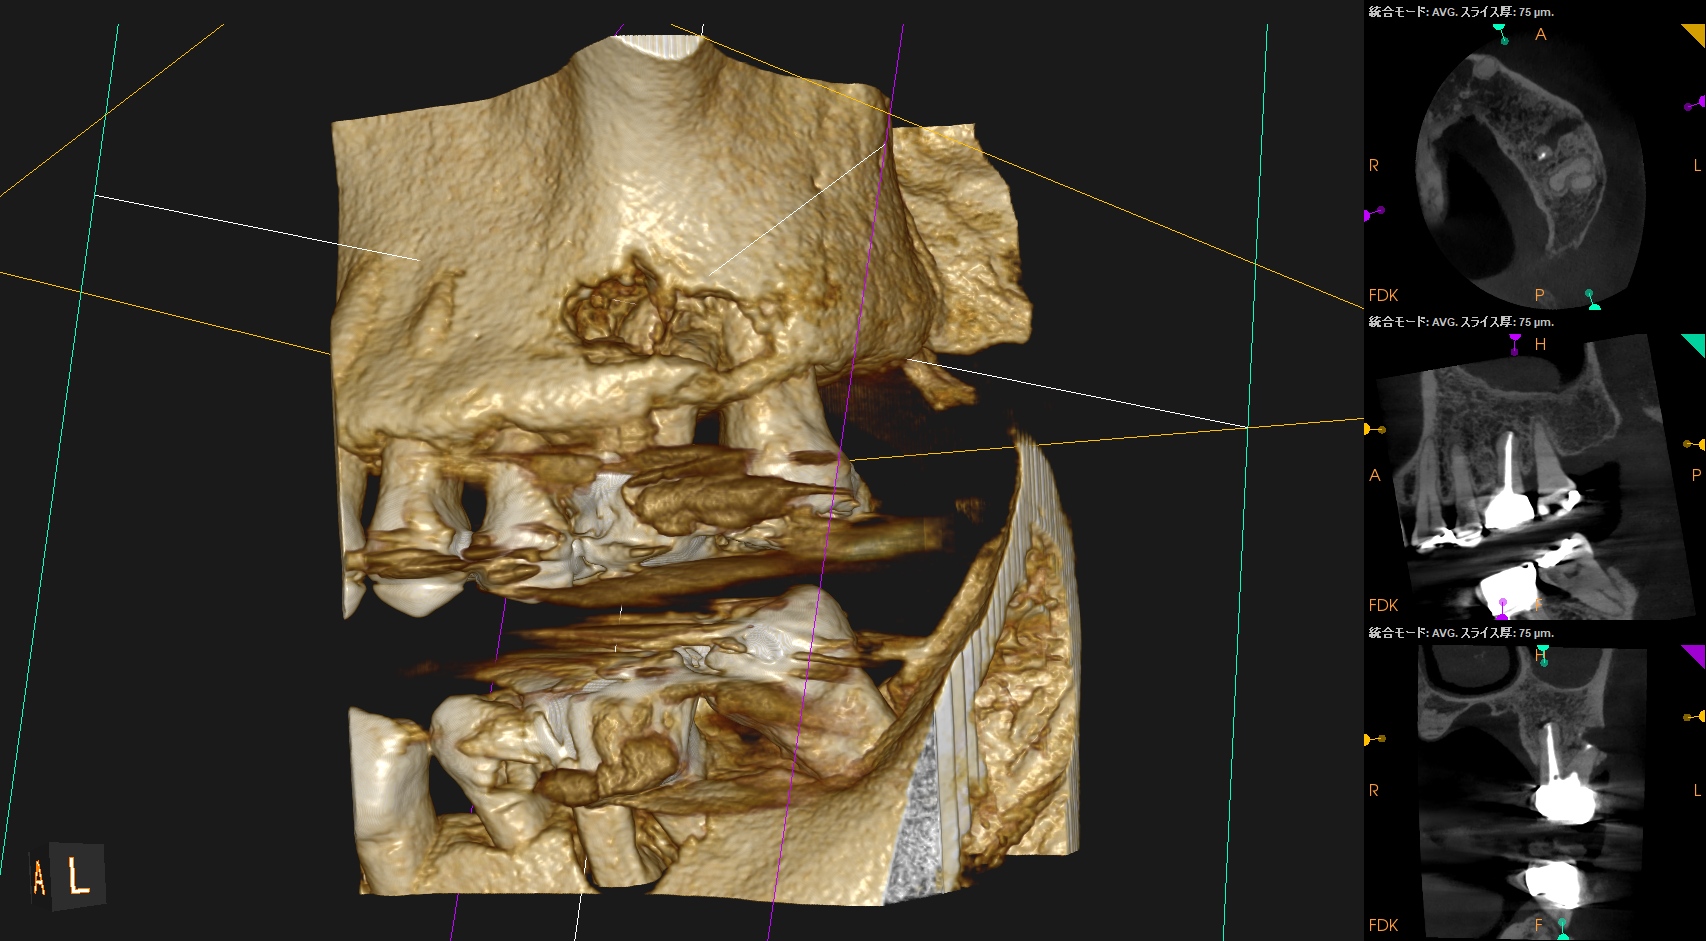

逆根充後にPA, CBCTを撮影した。

MB

DB

P

B